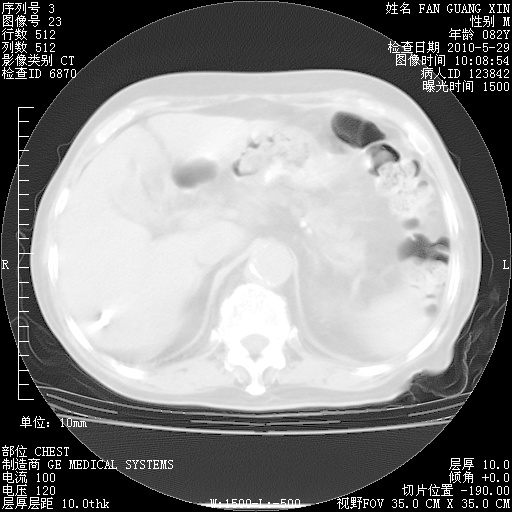

再治疗10天后的肺部CT 纵膈窗

从白细胞总数和中性比例看好像合并感染。肺部纹理好像比上次多,支气管炎?其他感染?

阅读此次胸部CT,肺间质渗出性改变较入院时有吸收。目前从体温、白细胞、中性分叶明显增高,肯定存在细菌感染(发生医院感染哦,若无消化道及泌尿系统等感染的依据,肺部感染可能大)。若你院头孢哌酮舒巴坦钠耐药率较高,同意你的方案,若48小时体温仍高,可考虑使用碳青霉稀类抗菌药物,同时可予超声雾化、注意滴数时加大液体量。白蛋白33.30g/L较低哦,需加强营养等支持治疗。